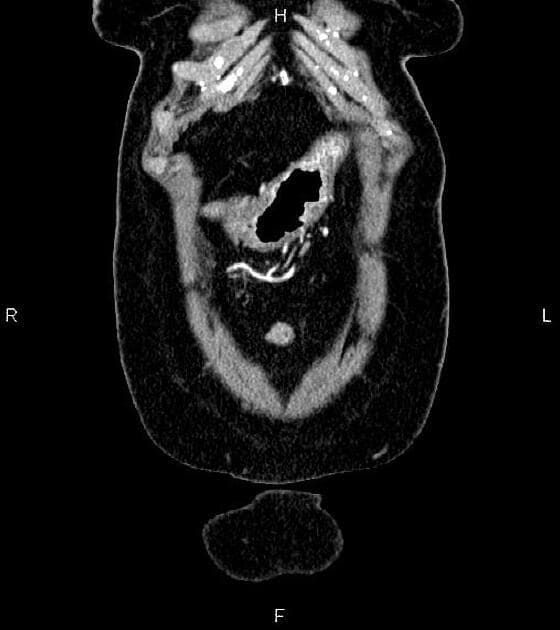

Axial C+ portal venous phase

- Khối dạng polyp ở đầu tụy gây giãn cả đường mật trong gan và ngoài gan.

- Khối dạng polyp ở đầu tụy (polypoid mass in the pancreatic head)

- Giãn đường mật trong gan và ngoài gan (dilated both intra- and extra-hepatic biliary ducts)

Khối dạng polyp ở đầu tụy đã được chứng minh trên mô học là u tuyến ống tụy (pancreatic tubular adenoma).

U tuyến ống tụy là một khối u lành tính hiếm gặp bắt nguồn từ biểu mô ống tụy, thường thấy ở đầu tụy. Khối u thường biểu hiện như một khối dạng polyp và có thể gây tắc mật, vàng da do nằm gần nhú tá lớn. Trên hình ảnh học, khối u hiện diện như một tổn thương ranh giới rõ, tăng tỉ trọng ở đầu tụy kèm giãn đường mật. Mặc dù các đặc điểm hình ảnh có thể giống với các tổn thương ác tính như ung thư biểu mô tuyến ống tụy hay u nhầy nội ống tụy (IPMN), bản chất lành tính được xác nhận bằng giải phẫu bệnh với cấu trúc tuyến dạng ống không có dị sản đáng kể. Cắt bỏ hoàn toàn khối u thường mang lại kết quả điều trị triệt để và tiên lượng lâu dài rất tốt.